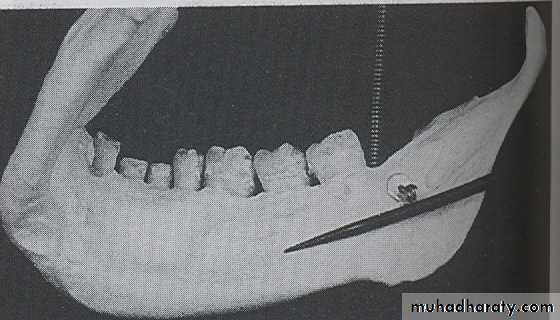

EXTERNAL OBLIQUE LINE :

The external oblique line is linear prominence of bone located on external surface of the body of mandible, the anterior end of ramus ends in the external oblique line. Radiographically the ridge appears as radiopaque band extending downward and forward from the anterior border of the ramus, its ends in the mandibular third molar region.

CORONOID PROCESS:

The coronoid process is a marked prominence of bone on the anterior ramus of mandible. Radiographically the coronoid process is not seen on mandibular periapical radiography but dose appears on maxillary periapical film as triangular radiopacity superimposed over the maxillary tuberosity region.